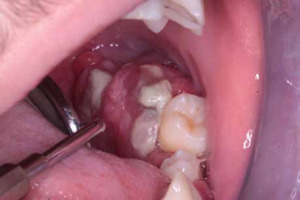

When the patient was 10, the exposure of two-thirds of palatal roots and third-degree loosening of teeth were observed (Fig. 3). A panoramic radiograph picture was taken (Fig. 4), which revealed complete absence of the bone base in all permanent first molars. Teeth 16 and 26 were qualified for extraction, which was performed in an outpatient setting under local anesthesia and antibiotic treatment (clindamycin, 10 mg/kg/dose). The obtained material from granulomatous lesions was submitted for histopathological examination, the results of which indicated non-specific inflammatory granulation tissue.